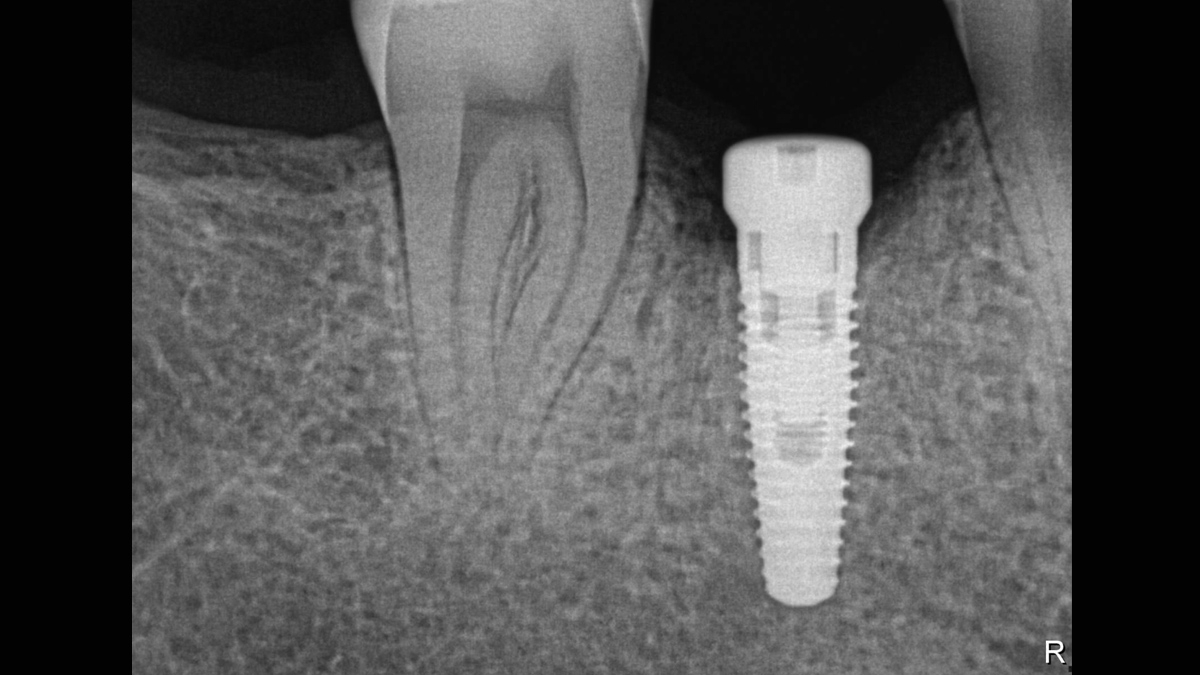

Os sensores Xios XG Supreme oferecem o melhor fluxo de trabalho e a melhor qualidade de imagem. O tamanho dos sensores pode ser adaptado para uso na rotina de trabalho do seu consultório. Eles ainda garantem o mais alto grau de eficiência em raios X. Com 33Lp/mm* e um cintilador CSI, isto é o que o Xios XG Supreme oferece acima de tudo: baixo ruído, contraste excelente e imagens de raios X em alta resolução para seus diagnósticos em segundos. É por isso que ele é ideal para ser usado diretamente na sala de tratamento. Xios XG Supreme é sinônimo de raios X intraoral moderno no mais alto nível.